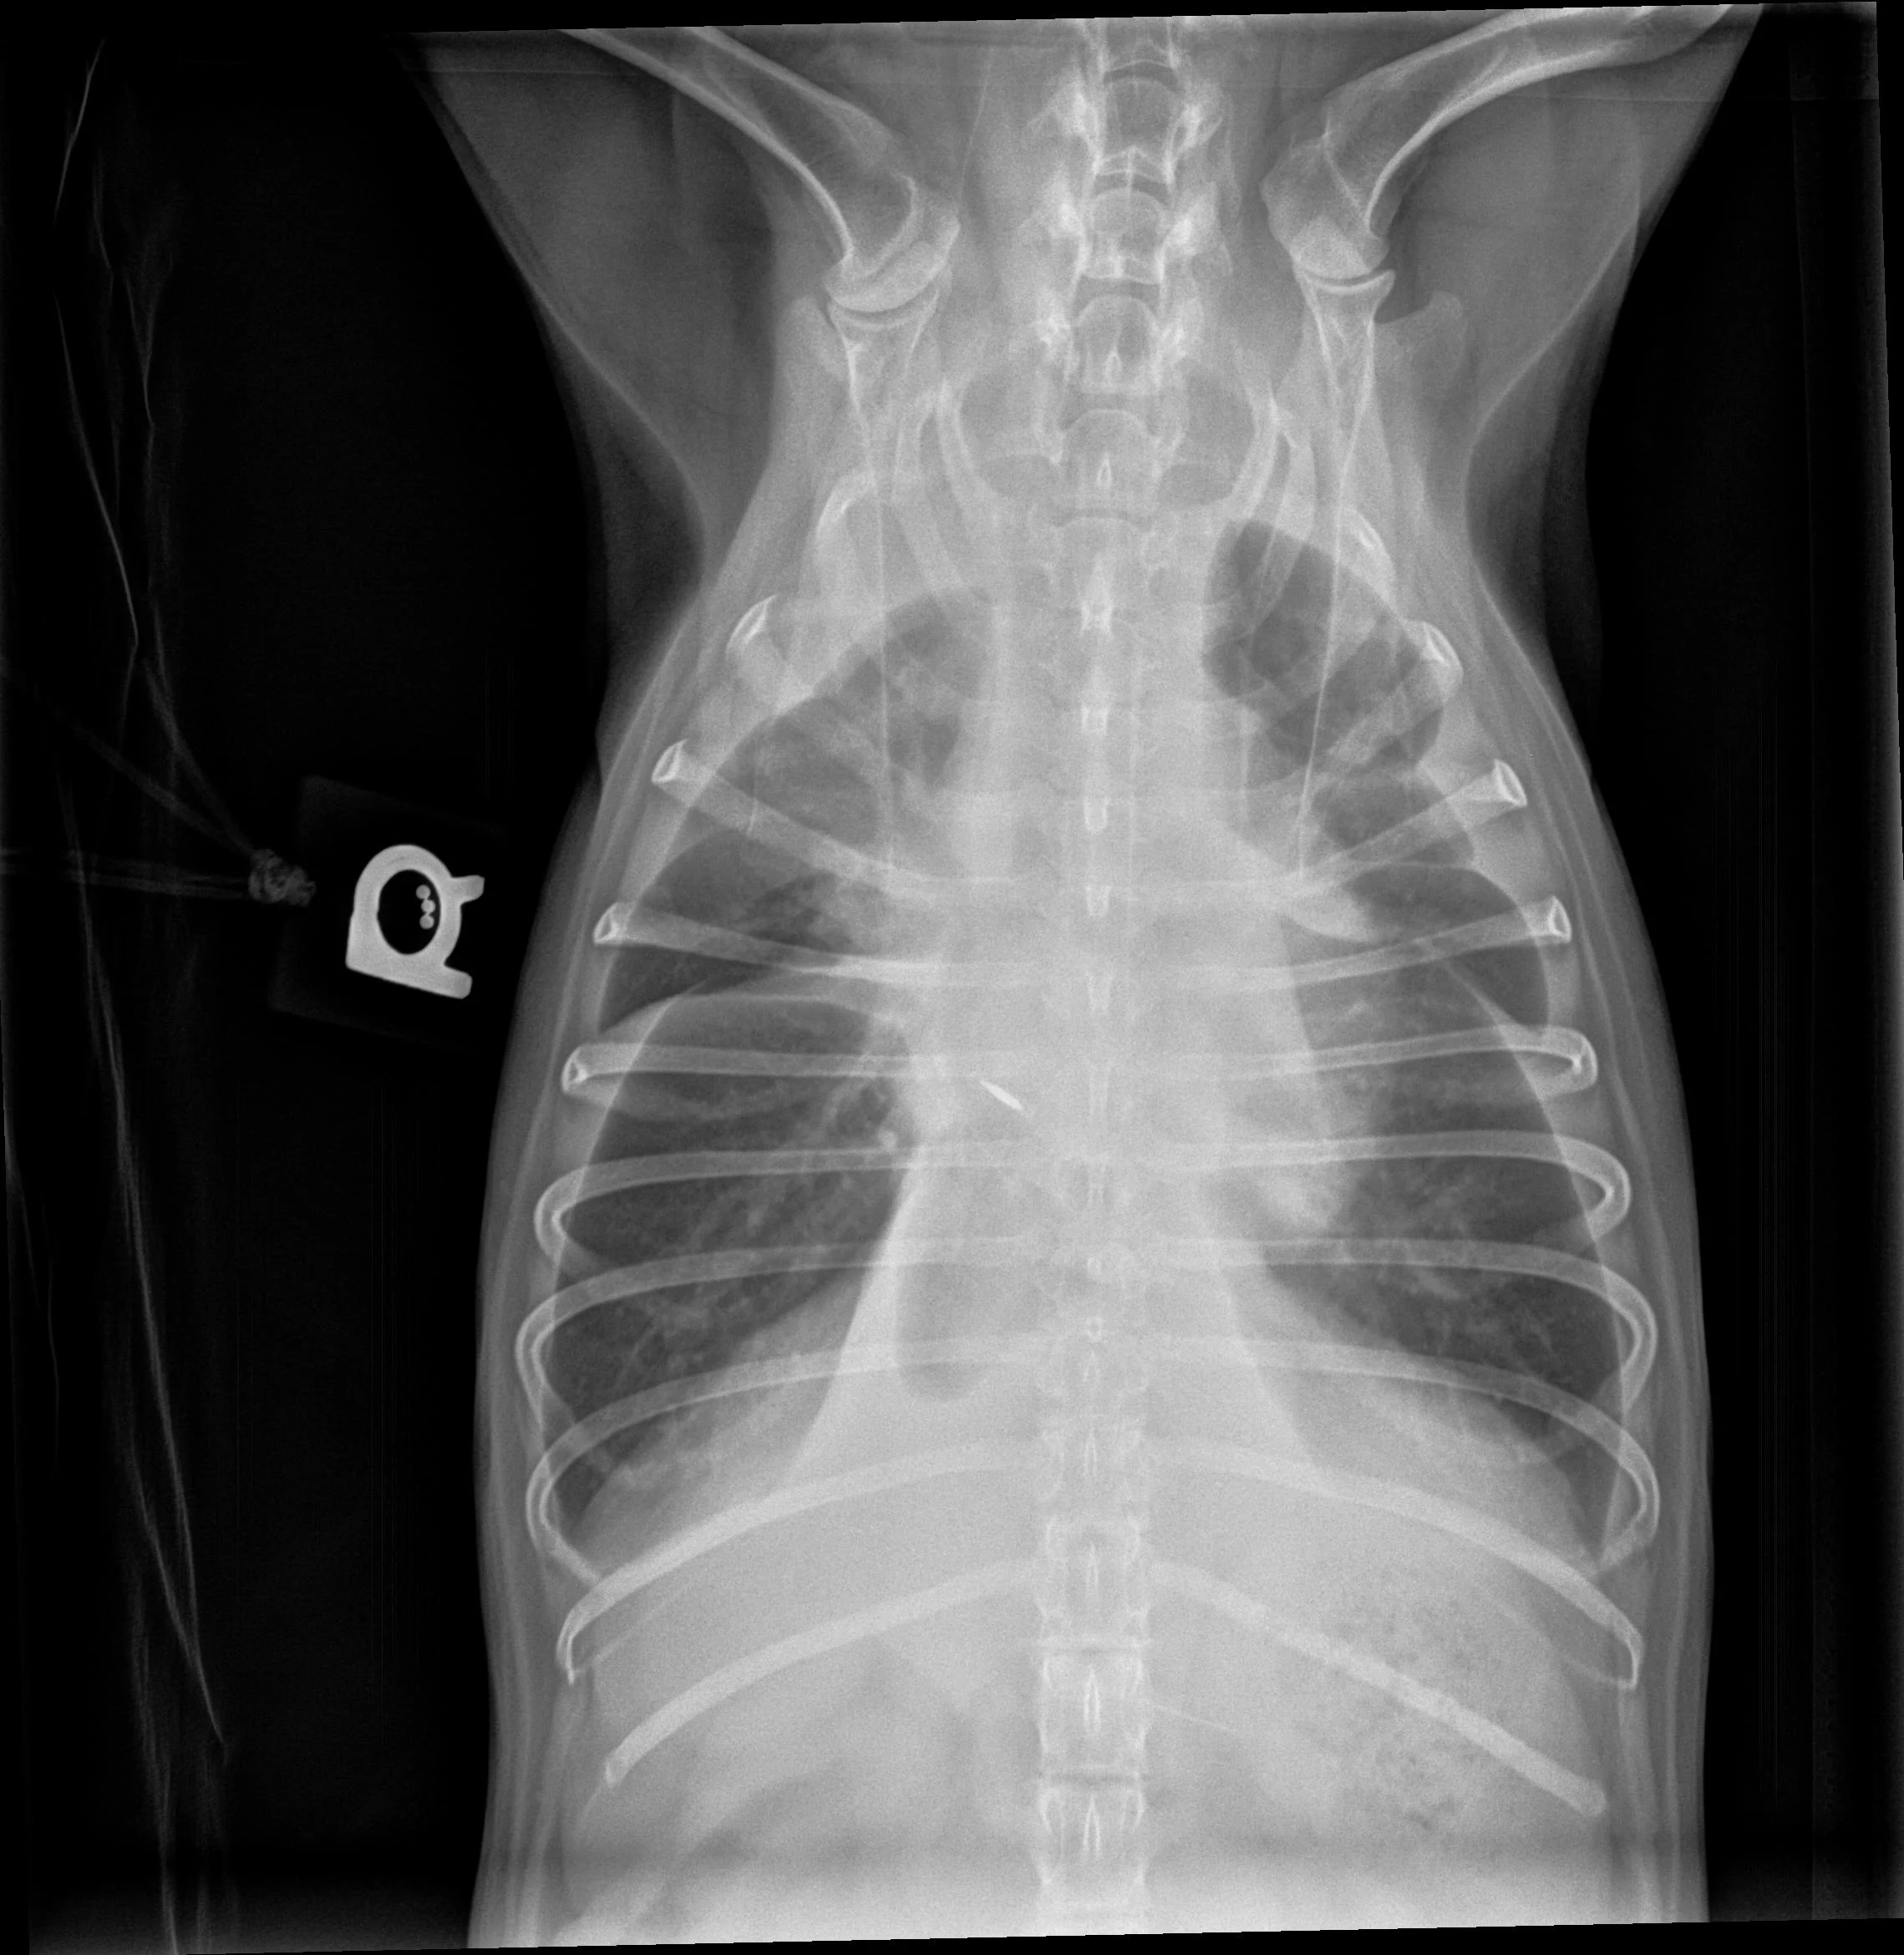

Pleural effusion can be easily identified on radiographs (Figures 1 and 2) and ultrasound (Figure 3). In patients with respiratory distress, oxygen and sedation should be administered before standard aseptic, often ultrasound-guided, thoracocentesis is performed. Removal and collection of fluid can quickly improve oxygenation and ventilation and allow clinical investigation to determine the cause of effusion.

Ventrodorsal radiograph of a dog with mild to moderate pleural effusion